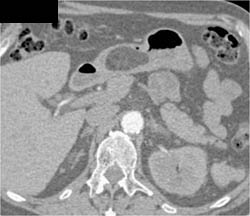

GIST Tumor